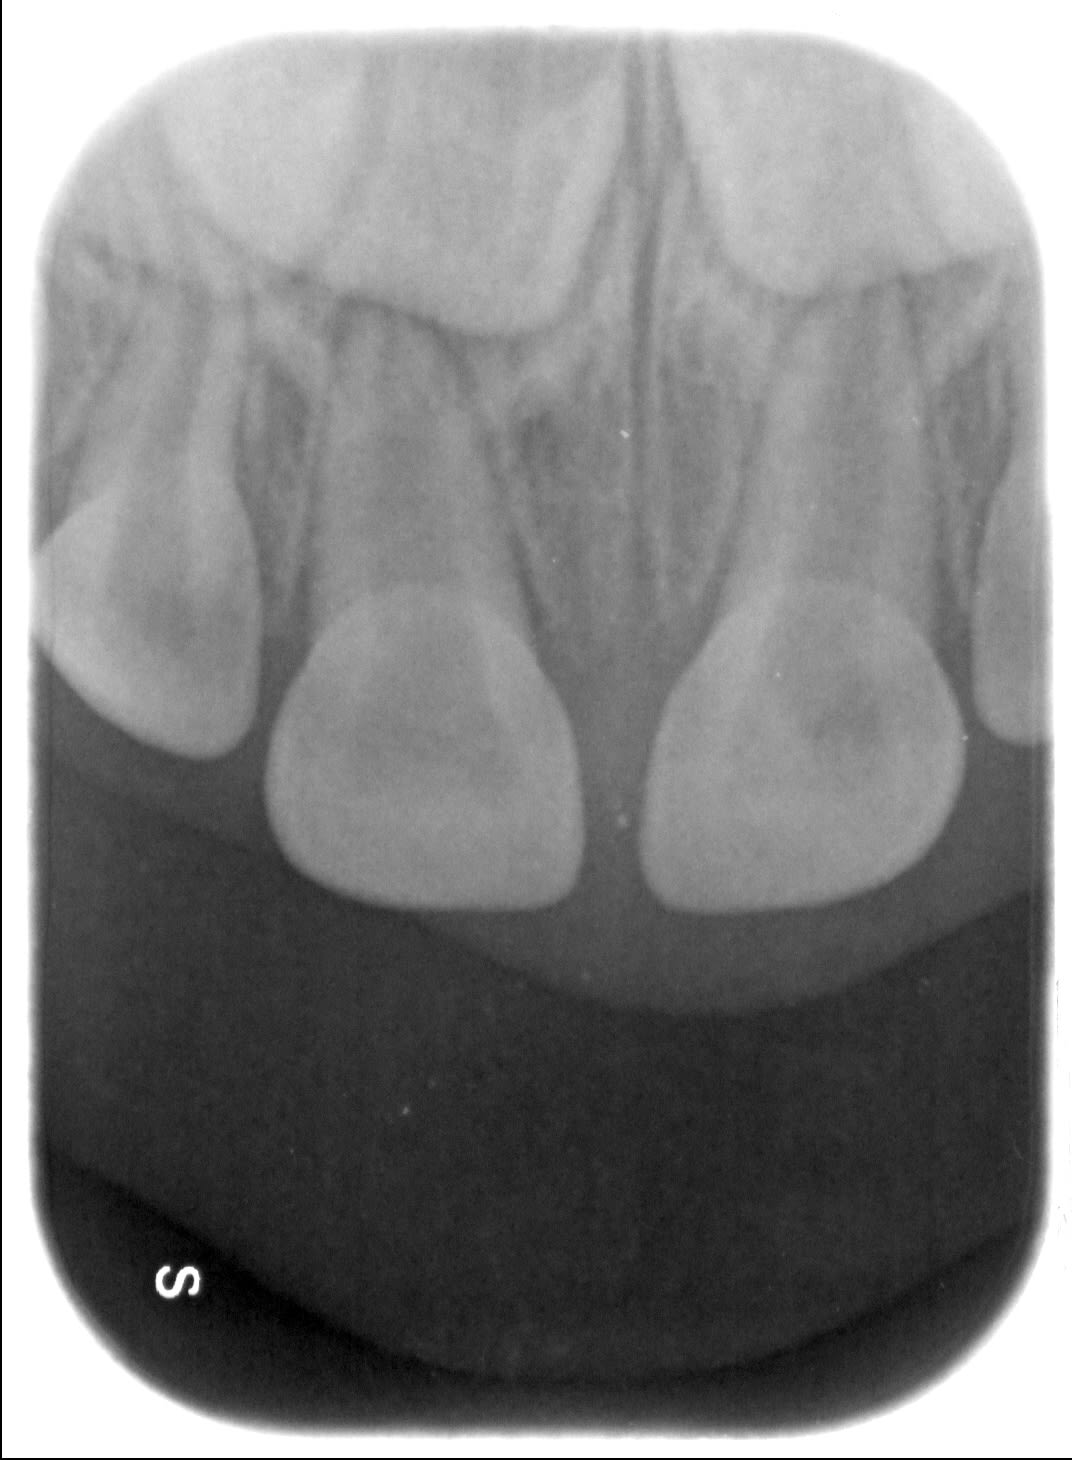

Garçon de 2 ans 11 mois, chute sur la face, peu de douleur, pas de mobilité, saignement sillon de 51.

Je ne vois rien de particulier à la radio.

Diagnostic de concussion je pense,

Il faudrait l'avis d'un pédo, mais en ce qui me concerne dans ce cas je fais une simple surveillance tous les 6 mois, y compris radiographique. Ce genre de trauma est extrêmement fréquent, les minéralisations ou nécrose des incisives lactéales consécutives sont aussi forcément très fréquentes. Les complications sont rares car la nature est plutôt bien faite sur ce coup là. La complication la plus évidente est un réveil infectieux aigu ou l'apparition d'une parulie (fistule) à l'apex, la plus vicieuse est la formation d'un granulome/kyste sans aucun symptôme clinique, avec déviation du germe de la centrale, indiquant l'avulsion de la dent lactéale concernée. Vu une fois en 12 ans.

Trauma à 2 ans, rvg à l'âge de 3 ans puis 5 ans (avulsion indiquée) puis à 7 ans.